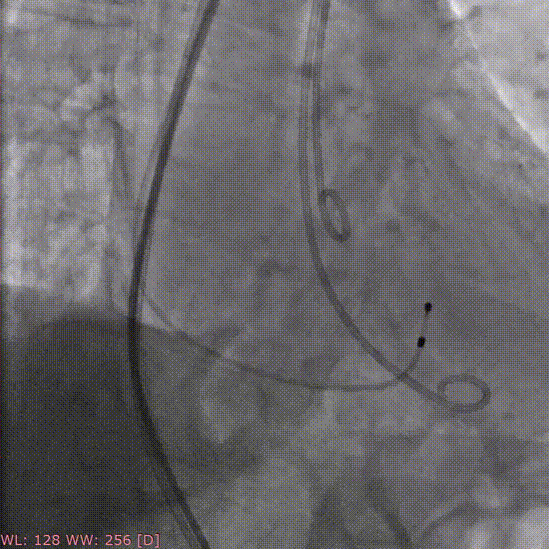

术前造影

定位件入窦

释放瓣膜

术后造影

术中经股动脉切开建立血管通路,患者为单纯反流患者,无明显钙化,无需球囊预扩张,术中建立轨道后直接将输送器送入主动脉瓣目标位置,轻松实现定位件的正确入窦,后成功释放28mm瓣膜。经DSA造影和超声等综合评估显示瓣膜释放位置完美,瓣膜工作稳定,术后即刻主动脉瓣反流消失,人工主动脉瓣瓣环内无反流,无瓣周漏,患者临床症状和血流动力学明显改善。